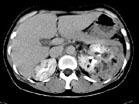

问题 女,36岁,左侧腰痛2 年余,CT检查如图所示,下列说法错误的是 ( )

选项 A、考虑为肾癌 B、考虑为双肾错构瘤 C、左肾病灶中可见脂肪密度灶,该区增强时也无强化 D、右肾中极可见一小的类圆形混杂密度病灶 E、左肾下极可见一混杂密度病灶,其边界尚清

答案 A